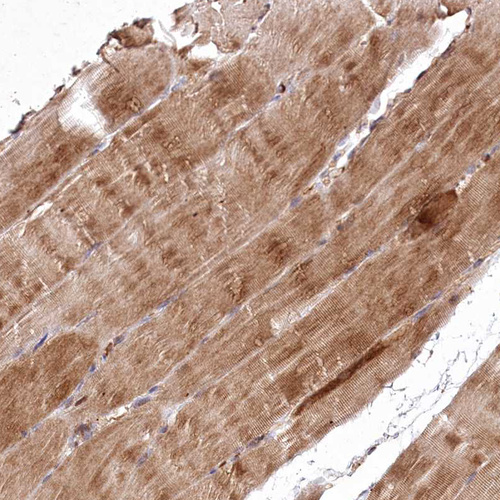

Immunohistochemical staining of human liver shows moderate granular cytoplasmic positivity in hepatocytes.